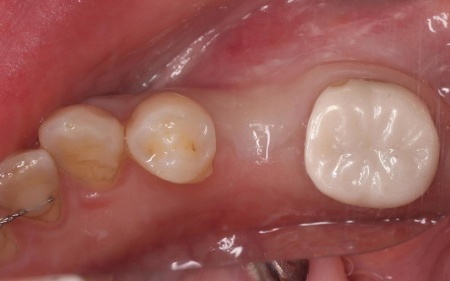

30代女性 歯根が割れた左上下奥歯を抜きインプラント治療で噛み合わせを回復した症例

拝見したところ、左上奥歯(第1小臼歯)は歯の上の部分である歯冠が折れ、歯根のみ残っている状態でした。

また、左下奥歯(第2小臼歯)には被せ物が装着されています。

レントゲン撮影をして痛みの原因を詳しく検査したところ、左上下奥歯の歯根が割れており、その影響で痛みが出ていると考えられました。

以上のことから、温存が難しいと判明している左上奥歯は抜き、左下奥歯は被せ物を取り外して内部を確認したうえで、適切な処置を行うことが望ましいと診断しました。

診断結果をお伝えし、患者様の了承を得たうえで左下奥歯の被せ物を外したところ、レントゲン検査での診断どおり、歯根が割れていることが確認できました。

そのため、患者様には左上下奥歯とも温存が難しい旨を説明し、抜歯に同意いただきました。

まず、左上下奥歯を慎重に抜きます。

続いてインプラント手術を実施し、インプラントを正しい位置と角度で顎の骨に埋め込みました。

インプラント手術後は経過観察を行い、インプラントが顎の骨に結合したことを確認したら、インプラント上部に取り付ける人工歯を作製するために精密な型取りを実施します。

後日、完成した人工歯をインプラントに装着し、使用感や見た目に問題がないことを確認して、治療を終了しました。